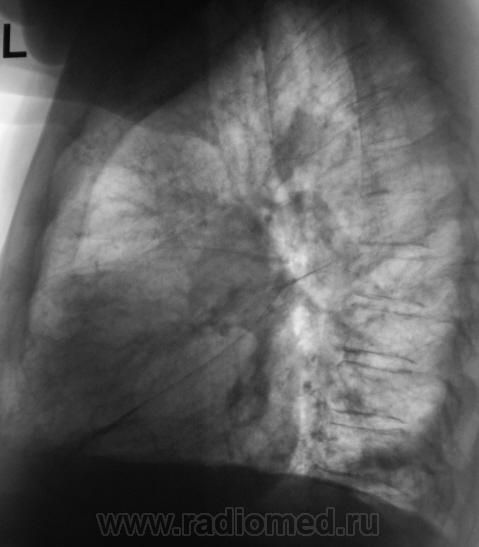

Произведены томограммы.

Здравствуйте Almo! Томограммы выполнены в стандартных срезах - 7, 9, 11 см.

Эта штучка неотделима от правой промежуточной артерии...

Вот раздумываю послать на КТ или не посылать. Пациент ничего и слышать не хочет о поездке в областной центр.

А что там в легких: фиброз, склероз, диссеминация? Почему этого не видно на томо?

На "томо" шикарно видно:

1. Гиповентиляцию правого лёгкого.